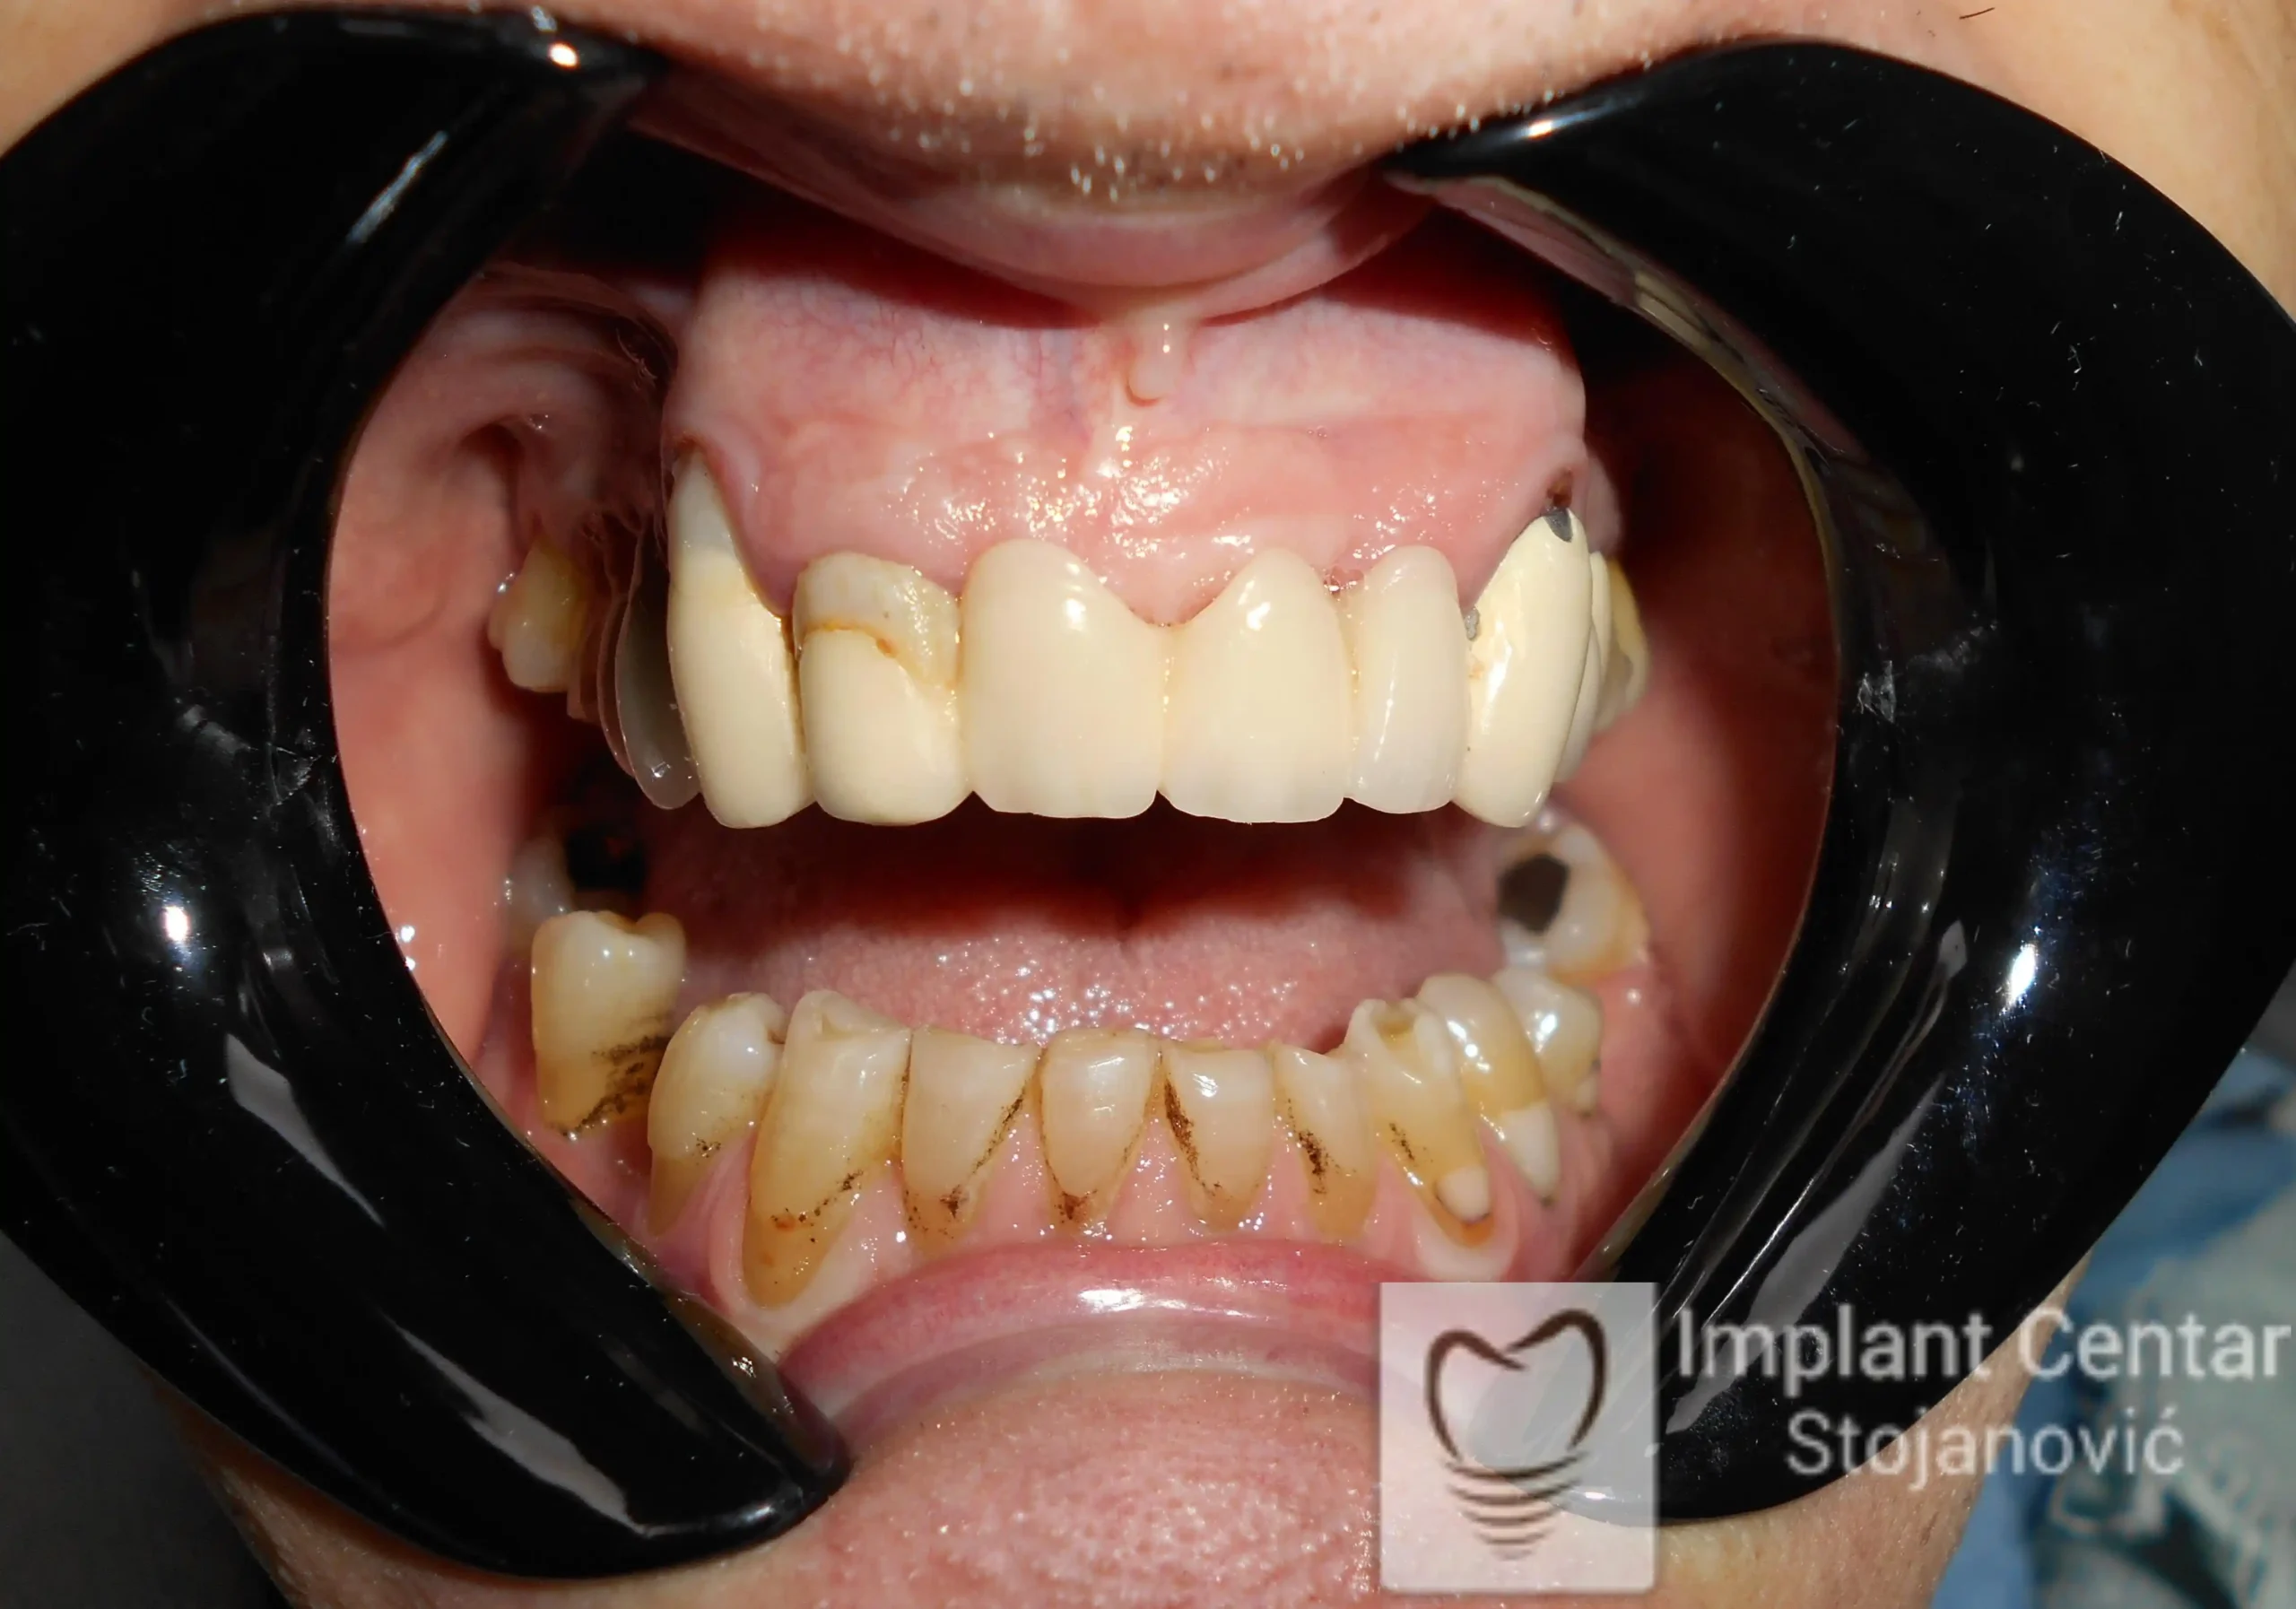

Na slici 1. i slici 2. prikazan je izgled pacijenta pre početka terapije – klinički i rendgenološki.

Nakon vađenja zuba, ugrađeni su implantati. Na slici 3 prikazan je ortopan snimak sa ugrđenim implantatima. Tokom perioda osteointegracije, pacijent je bio zbrinut fiksnim privremenim krunicama na implantatima, koje su izrađene samo dva dana nakon hirurške intervencije.

Na slikama 5. i 6. prikazan je izgled definitivnih cirkonijum-keramičkih mostova na implantatima.

Pacijent je izuzetno zadovoljan — kako estetikom novog osmeha, tako i funkcijom, jer ponovo može bez problema da jede i da se smeje.